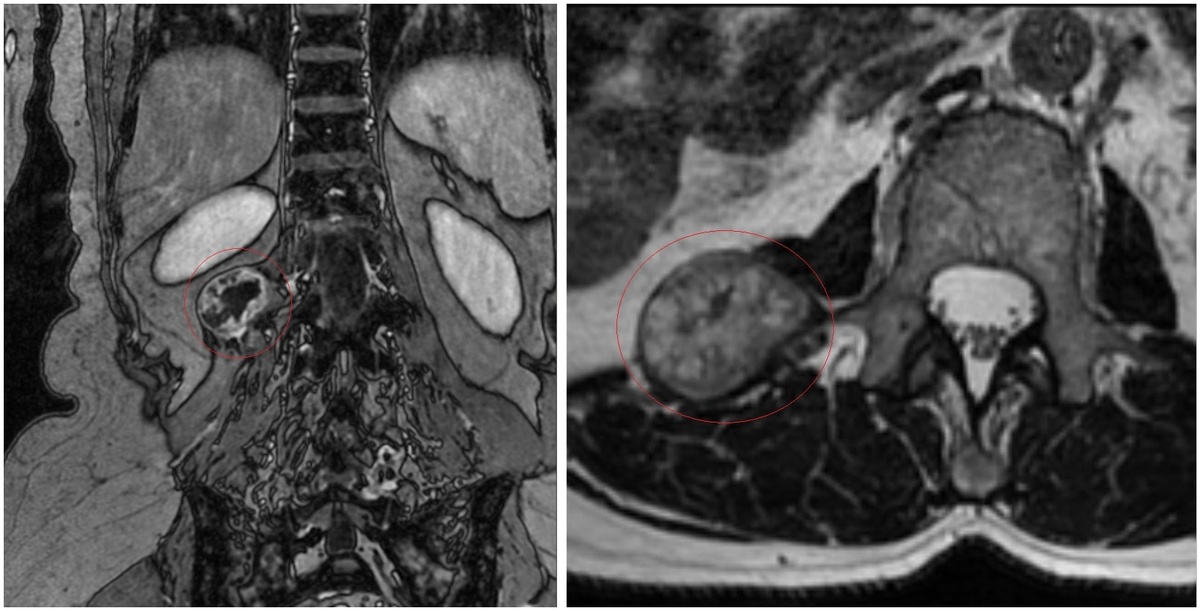

Магнитно-резонансная томография выявила паравертебральное (расположенное рядом с позвоночным столбом) объёмное образование размером около 3×4х3 см на уровне L1-L2 позвонков справа. Пациентка обратилась к врачу-нейрохирургу ННИИТО им. Я.Л. Цивьяна.

Опухоль выделена красным цветом

«Новообразование требует хирургического лечения, причём в этом случае не нужно делать предварительную биопсию — опухоль локализована и имеет чёткие границы. Пациентка согласилась на оперативное лечение, после оформления документов на квоту приехала на госпитализацию в ННИИТО и была прооперирована. Мы осуществили малоинвазивный доступ к опухоли сзади, выделили образование и полностью удалили. Опухоль отправлена на гистологическое исследование, однако по всем признакам, с большой вероятностью это будет невринома — доброкачественная опухоль»,